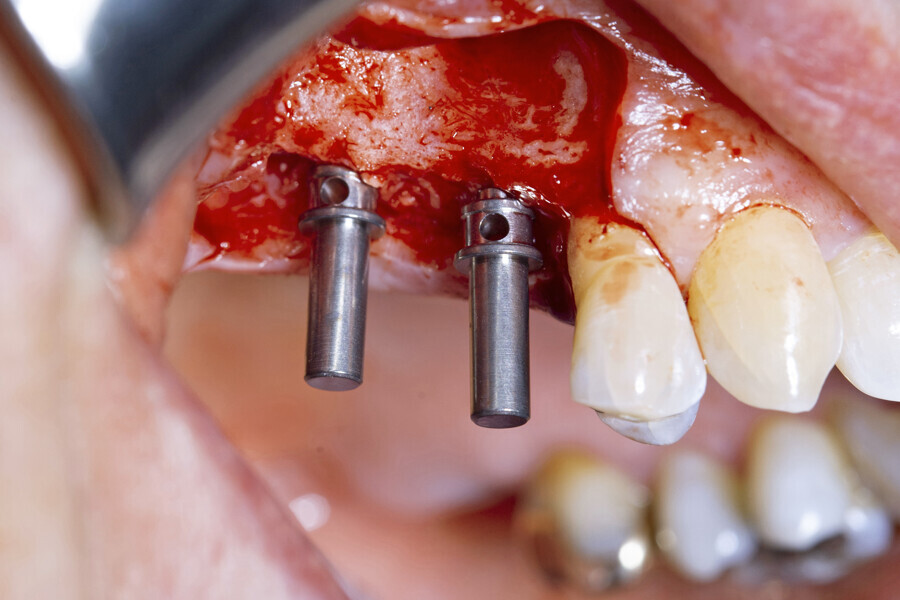

A full-thickness envelope flap was raised with relieving incisions, and the initial small round guide drill was used to mark the implant position. The site was enlarged with OmniTaper drills of different diameters, following the recommended drilling protocol. The initial osteotomy preparation was performed with a 2mm diameter OmniTaper drill at no more than 1,500 rpm and with copious external irrigation with saline according to the surgical protocol (Fig. 3). An OmniTaper EV 3.8 × 11.0 mm implant was placed in position #15 using the TempBase driver (Fig. 4). Both OmniTaper EV implants placed with the help of the preassembled TempBase abutments nicely aligned in positions #15 and 16 (Fig. 5).

Next, the large quantity of autogenous bone collected with the disposable BoneTrap (Dentsply Sirona) during surgery was used to augment the small bone fenestration (Figs. 6 & 7), and Symbios Xenograft Granules were layered over the autogenous bone (Fig. 8). Finally, Symbios Collagen Membrane SR (15 × 20 mm) was trimmed to shape to complete the guided bone regeneration procedure (Fig. 9). The wound was closed with PGA sutures (Fig. 10), and radiographic evaluation was performed to verify the implants postoperatively (Fig. 11). Three months later, medium Healing Abutments EV were placed (Fig. 12).

Fig. 5: Both OmniTaper EV implants placed with the help of the preassembled TempBase abutments nicely aligned in positions #15 and 16. Implant–abutment connection size of medium indicated in yellow.